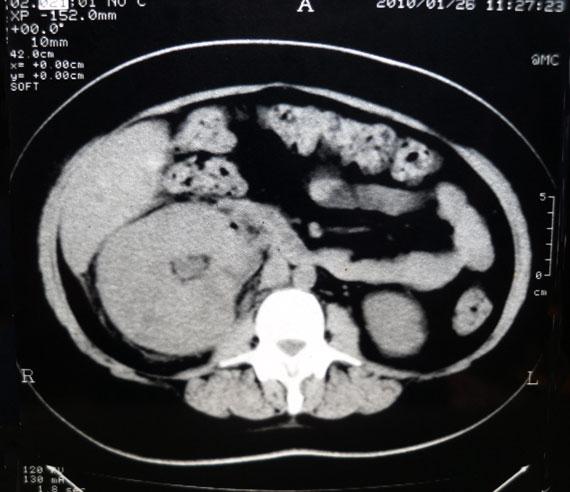

Chronological Photo-sequence

of the case progression

-On presentation: